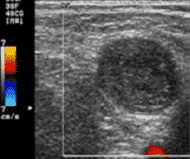

Detección de trombos y hematomas

La detección trombos y hematomas previos y posteriores a la canalización, evita realizar punciones sobre vasos ya dañados y optar por otros más adecuados y normo funcionantes.

En lo que a la técnica se refiere, también se utiliza la sonda lineal de alta frecuencia. En este caso es preferible el uso de Doppler a color, útil también para determinar permeabilidad, aunque también puede emplearse el modo 2D.

En la detección de trombos se puede observar una imagen ecogénica heterogénea que ocupa total o parcialmente la luz venosa y se considera un signo prácticamente patognomónico la imposibilidad de comprimir la luz vascular por completo. Además, si utilizamos Doppler a color aplicado sobre la luz vascular se apreciará ausencia de flujo o algún defecto de repleción.

Los hematomas dan una imagen similar a la del trombo, pero se encontrarán ubicados por fuera del vaso, pudiendo llegar a comprimirlo o desplazarlo.